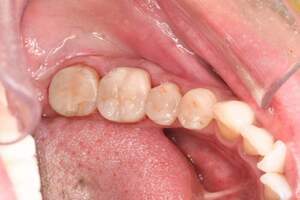

治療前:下の歯

担当医師所見:

下顎右側臼歯部には一見大きな問題はないように見えるが、 頰側にフィステルと言われる排膿路があり発赤と主張があり炎症状態が続いていた。

治療後:下の歯

下顎右側第1大臼歯は抜歯後、仮歯に置き換え治癒を待った後ジルコニアステイニングBrにて補綴。 全顎的に色調・形態共に調和がとれている。